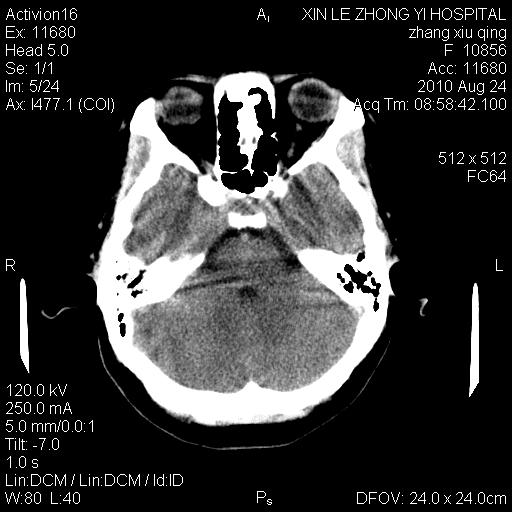

标题: CT28569:看看鞍上池正常吗 [打印本页]

标题: CT28569:看看鞍上池正常吗

女 24 偶有头晕

怎么这么多伪影?我感觉没什么特别异常哦,是不是伪影所至呀

伪影多,建议行mri!

没什么!只是扫描层面与听眦线不平行